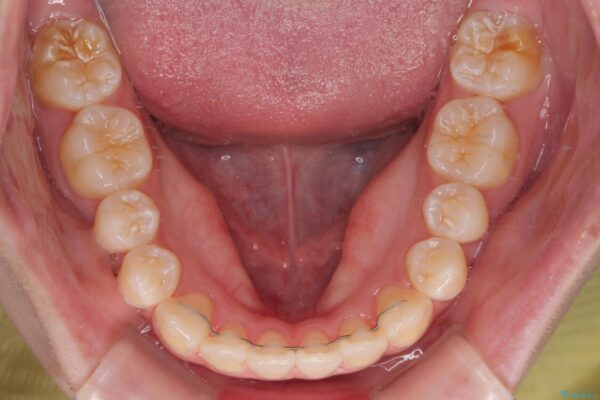

治療後

• 【モニター】前歯のデコボコをスッキリ解消!目立ちにくいワイヤー矯正でスピーディに治療完了 治療後画像

患者様の協力もあり、およそ1年間で治療を完了。スムーズな歯の移動を実現しました。

上下の正中(真ん中のライン)もずれることなく、バランスの取れた美しい歯並びに。笑顔に自信を持てる仕上がりとなりました。